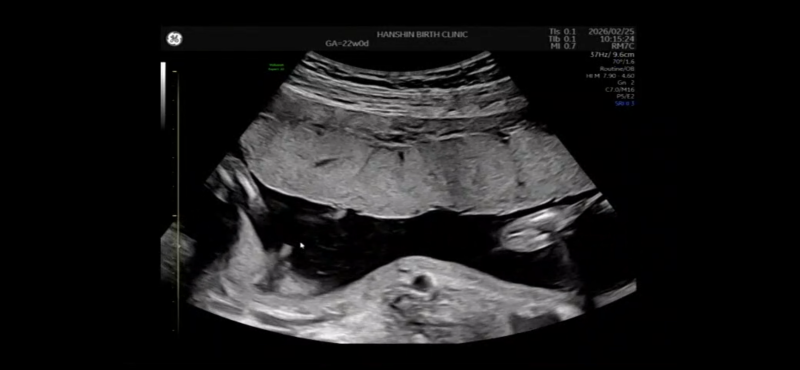

先日22週の検診で、「男の子っぽいけど週数的に女の子でも突起してる場合あるからどっちかなー?」と言われました!

先生はこの写真を見てどちらだと思いますか?

実際にエコーで拝見しているわけではないので、お写真からですと、なかなかはっきりとしたことはお話しできませんが、その時のお子さんの位置や向きによっても性別は見えたり見えなかったりします。

せっかくご相談いただきましたのに、はっきりとしたことを明言できず申し訳ありませんが、医師もまだ分からないとお伝えしているのであれば、はっきりとは見えていないのかもしれませんね。また再度健診の際にご確認なさってくださいね。